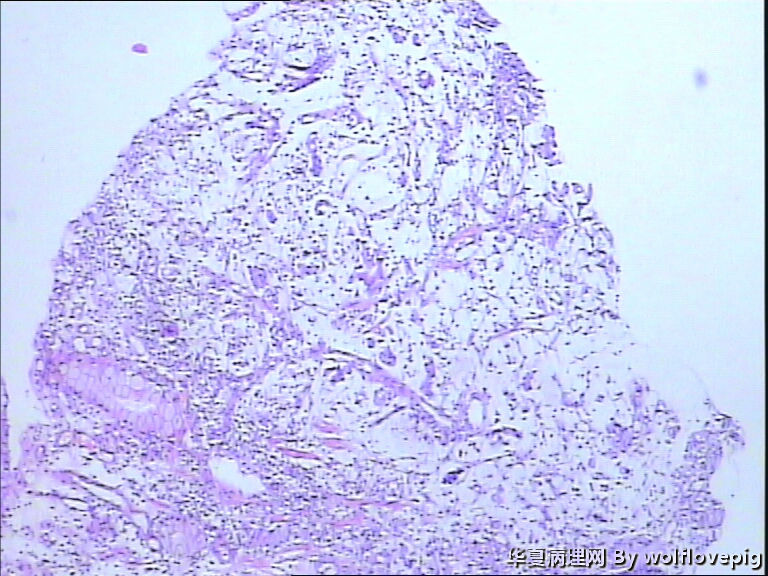

男,60y,胃窦呈结节样改变。

图2